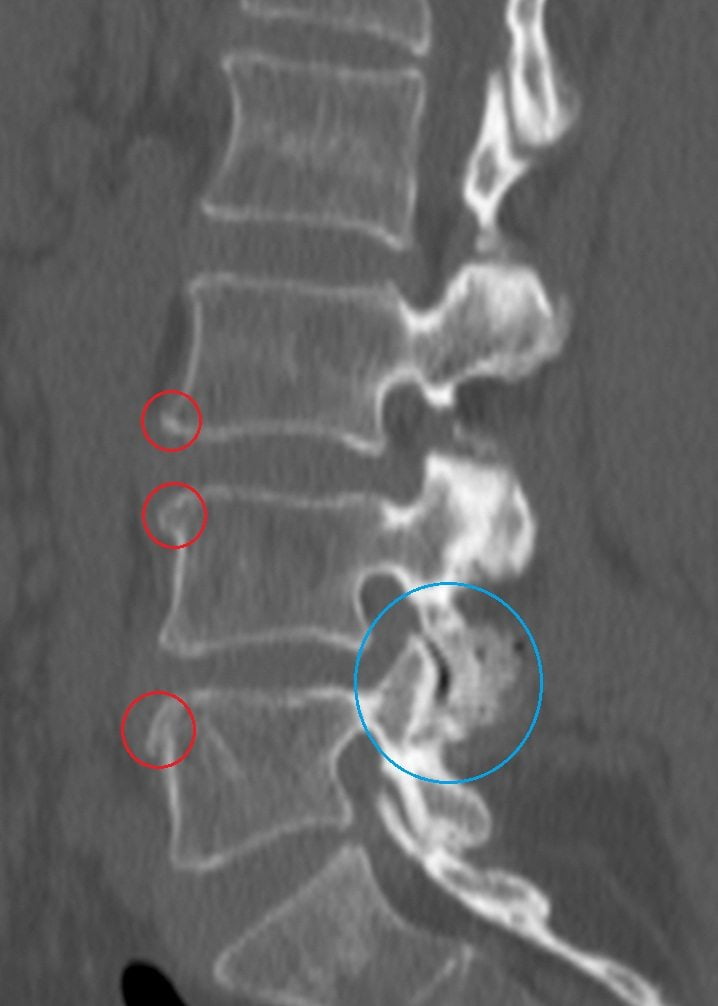

В народе распространено мнение, что мануальные терапевты вправляют «выпавшие диски». К сожалению, это массовое заблуждение. Межпозвонковые диски не могут выпадать. В них могут разве что формироваться грыжи, вправить которые невозможно.

Массаж и мануальная терапия эффективны при спондилолистезе – смещении позвонков. К сожалению, они оказывают лишь временное действие. В будущем съехавший позвонок скорее всего будет смещаться снова.